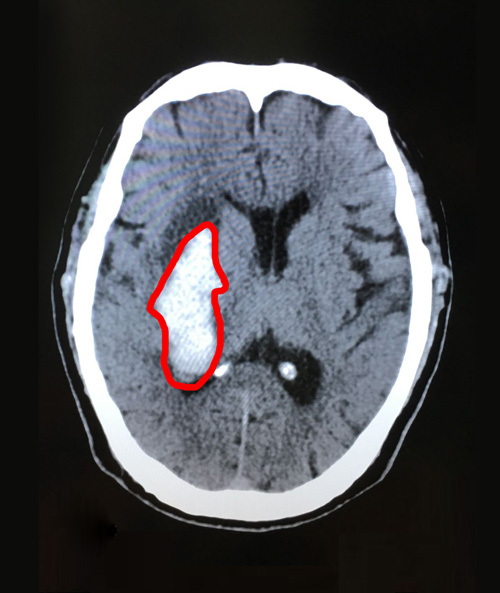

术前影像:右侧基底节区急性脑出血,右侧脑室后角少量积血